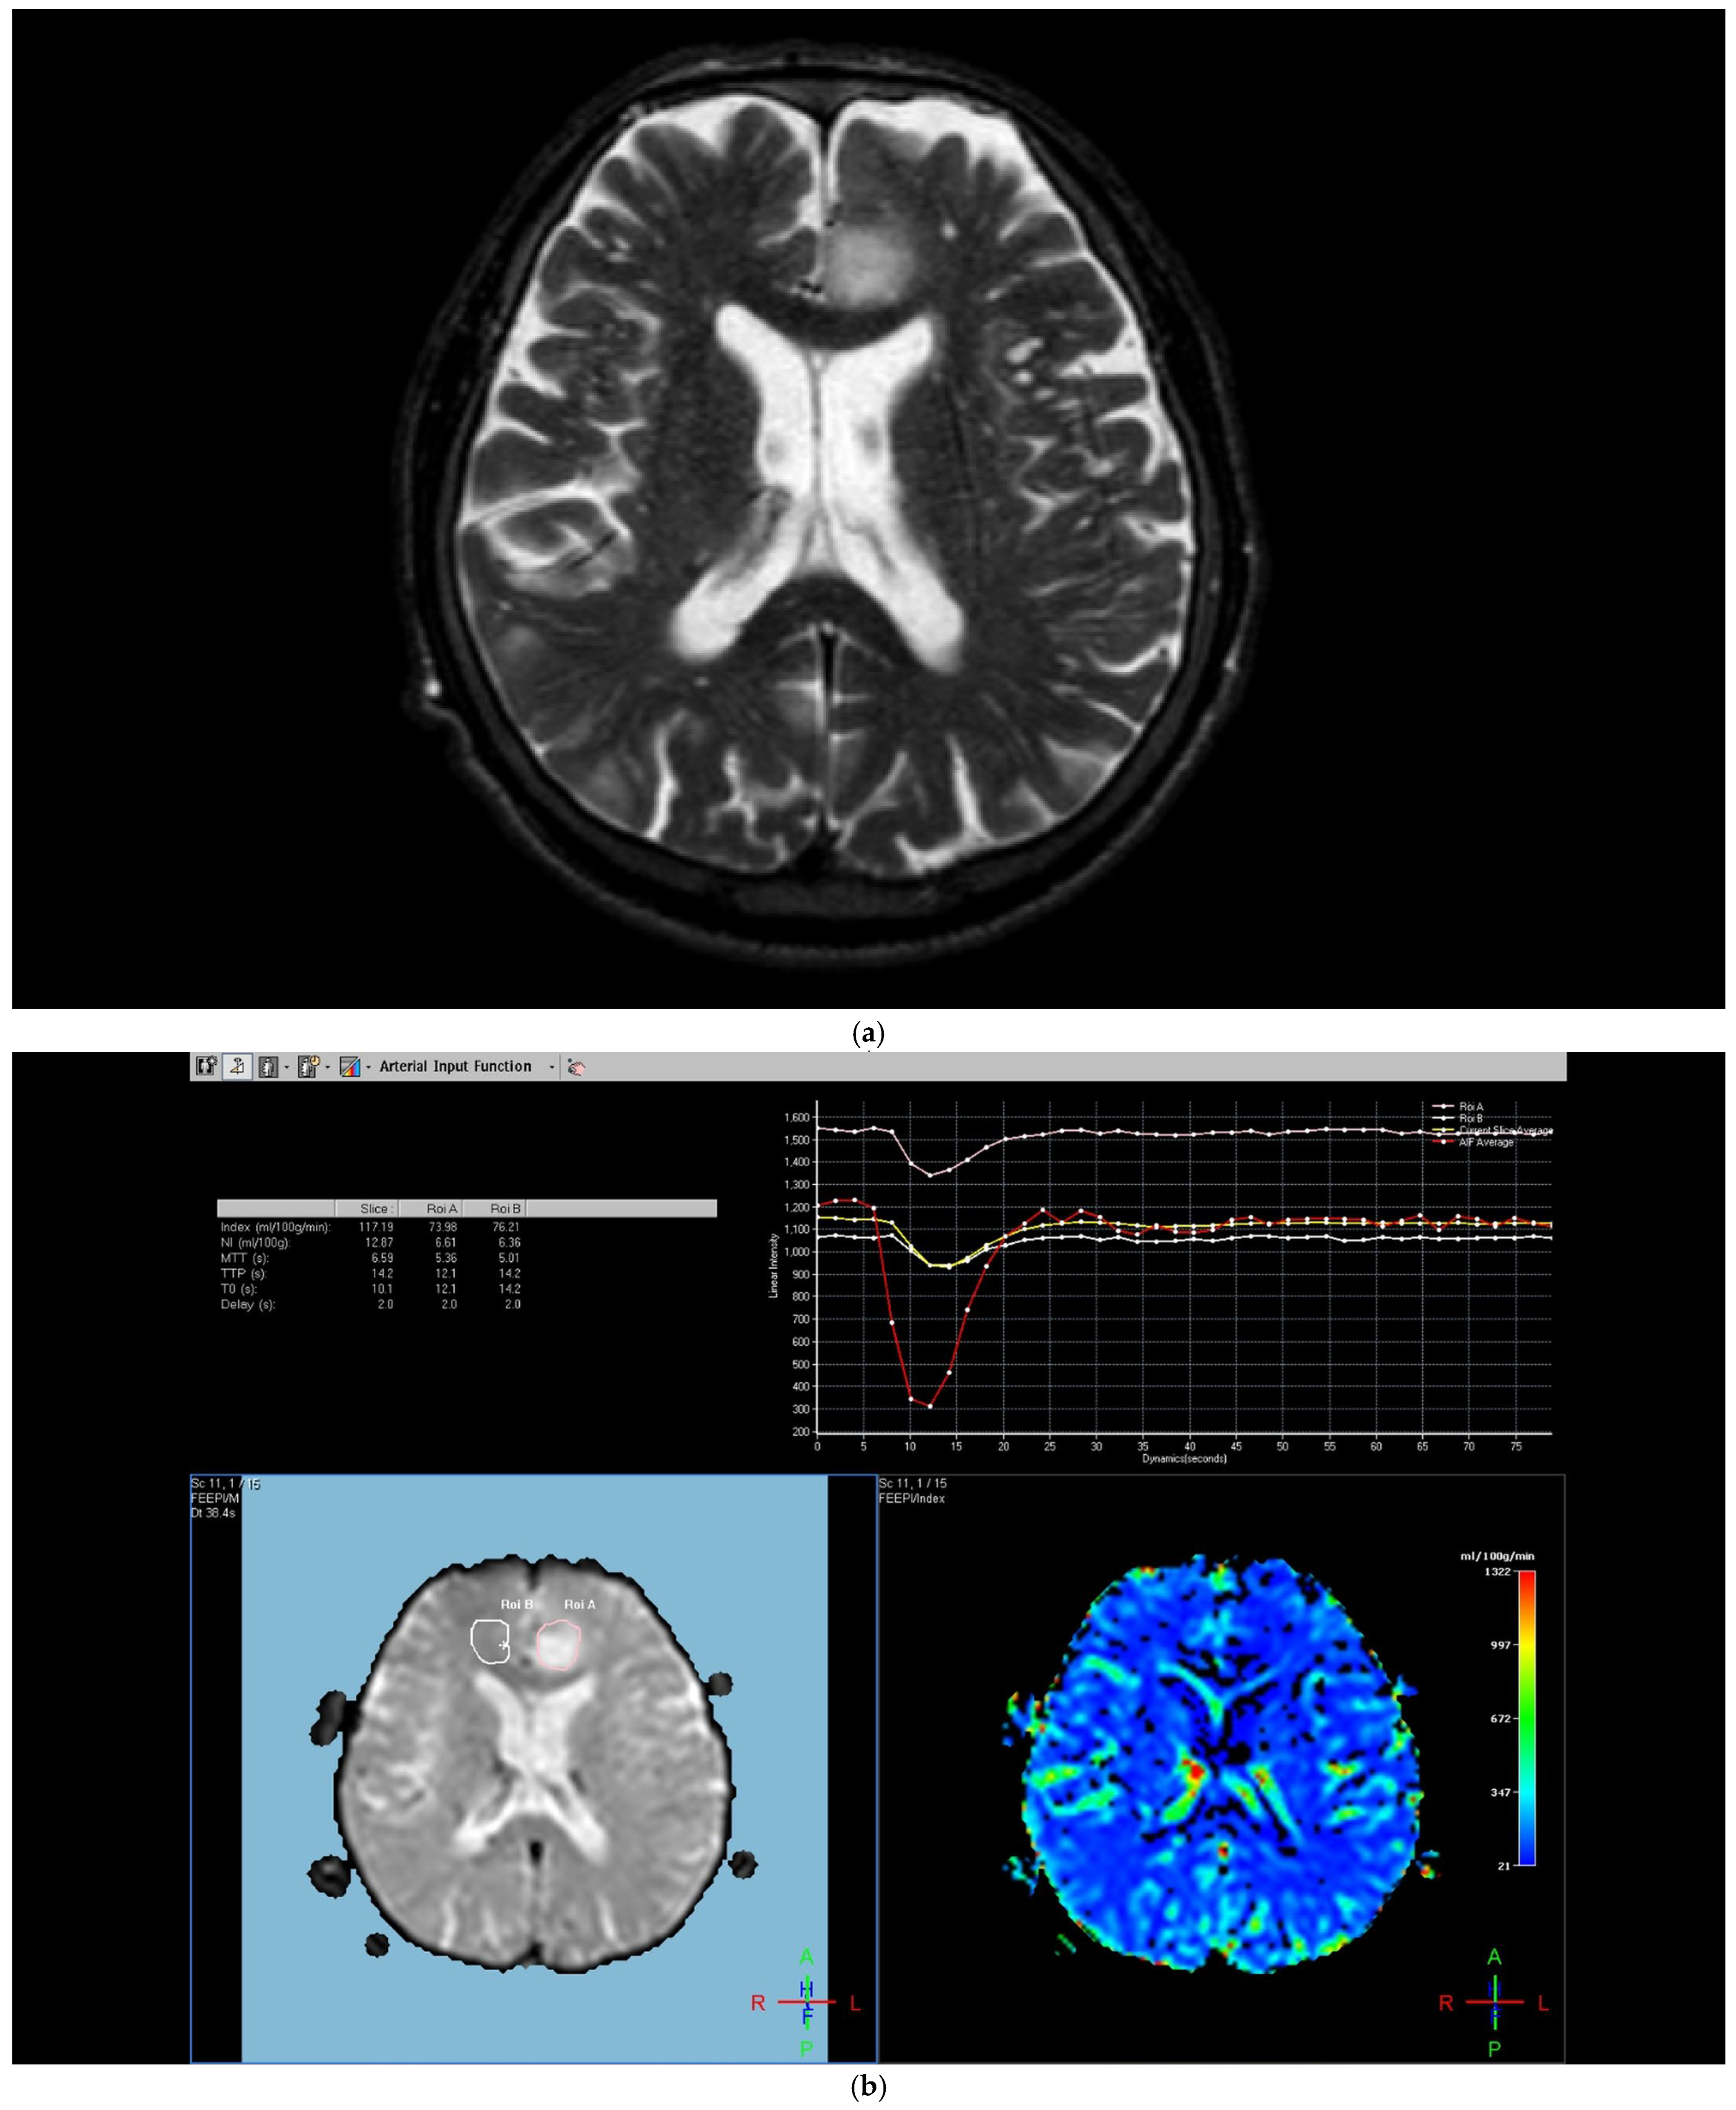

The region of interest (ROI) size ranged from 2 to 10 square millimeters in area, depending on the size of the tumor. rCBV values were obtained by identifying regions of maximal perfusion from color maps (Figure 1). While measuring the rCBV values, care was taken to avoid any vascular structures, cerebrospinal fluid, or areas with high susceptibility. For the appropriate placement of the ROI, the rCBV maps were coregistered with FLAIR/T2-weighted, post-contrast T1-weighted, or SWI/GRE images. For multiple metastatic lesions, the measurements were performed from the largest and most enhanced tumoral lesion.

Figure 1. Brain magnetic resonance imaging (MRI) of a 52-year-old male with a low-grade glial tumor revealed (a) increased signal on a T2-weighted image, (b) hypoperfusion with a rCBV of 1.08 in perfusion-weighted imaging, Pink ROI is from tumor and white ROI is from contralateral parenchyma. and (c) a total of four ROIs—one from the peritumoral region (in blue), one from the contrast-enhancing tumoral area (in pink), and two from the contralateral tumor-free white matter areas corresponding to these regions (in white and red) in perfusion-weighted imaging.